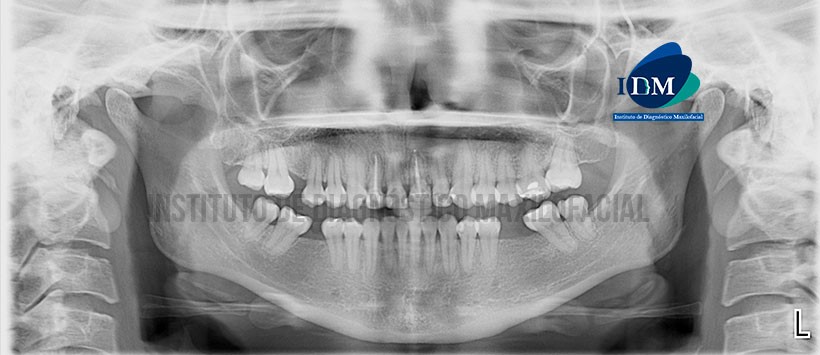

En la radiografía panorámica (Figura 1) se observa a las piezas 12 y 21 con restauración coronaria y obturación de conductos radiculares con aparente sobreobturación en pieza 21. Presencia de múltiples restauraciones y ausencias de piezas 16, 28, 36 y 46.